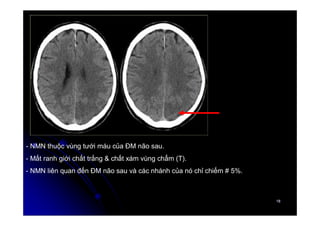

- NMN thuộc vùng tưới máu của ĐM não sau.

- Mất ranh giới chất trắng & chất xám vùng chẩm (T).

- NMN liên quan đến ĐM não sau và các nhánh của nó chỉ chiếm # 5%.